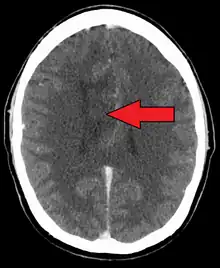

| A oligoastrocytoma on CT | |

An X-ray computed tomography (CT) or magnetic resonance imaging (MRI) scan is necessary to characterize the anatomy of this tumor as to size, location, and its heter/homogeneity. However, final diagnosis of this tumor, like most tumors, relies on histopathologic examination (biopsy examination).[3]